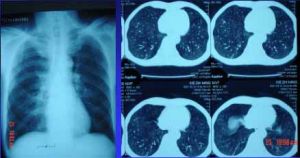

可見雙側瀰漫性顆粒狀陰影,自肺門向周圍伸展,呈毛玻璃樣,伴支氣管充氣象,以後變成緻密索條狀,間雜有不規則片塊狀影。後期有持久的肺氣腫,在肺周圍部分更為明顯。可伴縱隔氣腫及氣胸。

卡氏肺囊蟲肺炎在臨床上有發熱、乾咳和呼吸急促,特別在無活動時仍感急促,最終可致發紺和呼吸衰竭。體檢可見肋間、肋下、胸骨上凹和鼻翼潮紅,肺部體徵不明顯,聽不到哆音。 x線檢查,可在發病後 l天左右出現陽性體徵。典型胸片顯示兩肺瀰漫性肺泡病變,亦可有小葉浸潤。